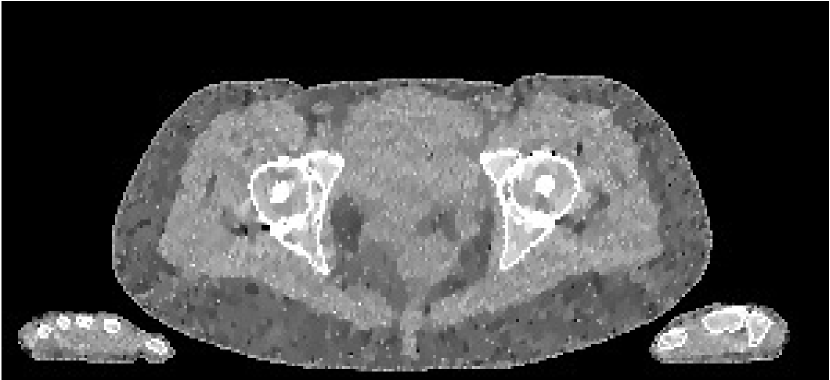

Refer to caption

(a) FBP metal

(b) PWLS metal

(c) Poly-SIR metal

(d) IMPACT metal

(e) Polyquant metal

Figure 12: Metal insert visualisation of slice 91 from CBCT reconstructions with display window [0.7,1.4]. The Poly-SIR is the version based upon segmentation from the PWLS as that in Figure 11(c)

Reconstructions of the 83rd slice from the CBCT data are shown in Figure 11, along with a region from the 91st slice containing a higher mass of metal in Figure 12. Although the FBP appears to suffer strongly from the presence of the metal structure, most of the iterative methods mitigate its effect considerably, with the PWLS showing a more pronounce dark region in the soft tissue. The Poly-SIR based on a segmentation from the FBP does suffer from its streaking as shown in Figure 11(d). Although a better performance is achieved through segmenting from the PWLS as in Figure 11(d), this will have a considerably higher total computational cost; the Poly-SIR region in Figure 12(c) is based on this PWLS initialisation. The preservation of bone structure appears to be similar between all the iterative methods. The Polyquant method appears to have the smoothest regions around the metal implant, whilst maintaining the same level of structure in the bone and objects surrounding the phantom.